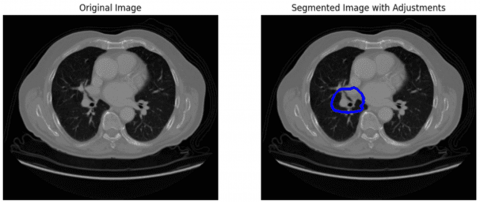

Further, image segmentation was done using the U-Net algorithm to isolate ROI from the preprocessed images [28]. This technique has the potential to segment the regions with training using less data. It consists of three main elements namely: encoder, bottleneck, and decoder. The encoder component down-samples the preprocessed images through convolution and pooling operations and maps the regions within each image. The bottleneck is placed between encoder and decoder and it maps the most informative regions while retaining spatial information. The encoder performs upsampling and reconstructs the image from the feature representation. The reconstructed image is the segmentation output. Figure 4 displays the segmentation outcomes.

Figure 4. Segmentation images